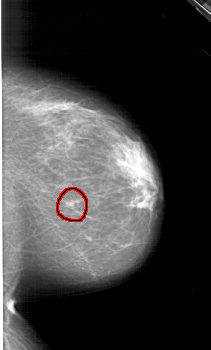

RIGHT_CC LINES 5941 PIXELS_PER_LINE 3571 BITS_PER_PIXEL 12 RESOLUTION 43.5 OVERLAY